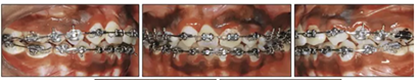

兩年半后,在上下牙弓上均實(shí)現(xiàn)了間隙關(guān)閉,并且使用0.017×0.025英寸的不銹鋼弓絲進(jìn)行咬合精細(xì)調(diào)整(圖8)。去除托槽后,上下頜采用舌側(cè)弓進(jìn)行保持(圖9)。